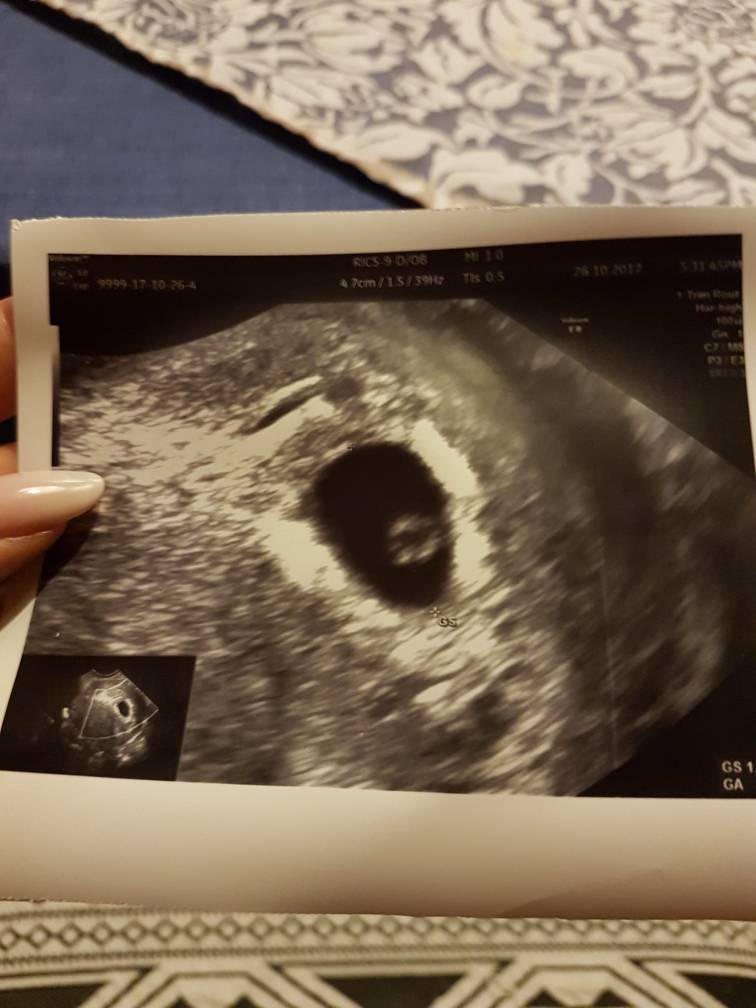

Zgodnie z obietnicą pisze - jestem po wizycie, trochę się martwiłam bo dzisiaj w sluzie nitki krwi ale po badaniu wszystko ok. "Książkowa szyjka, mięciutka macica, ładny mleczny sluz"pęcherzyk dopiero, na serducho jednak za wcześnie

Pieknie tętno było widać, pulsowało prawidłowo